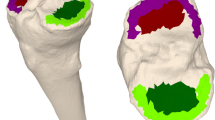

Pins with an infrared optical motion tracker were bicortically inserted in the tibial and the femoral bone. These trackers were oriented to be visualized by a knee navigation system (PrecisionN knee navigation system, Stryker Medical Systems, Duisburg, Germany) with special knee navigation software (Precision Knee Software, Stryker Medical Systems, Duisburg, Germany).

The Stryker PrecisionN knee (Fig. 1) navigation system which was developed to increase the efficiency of the total knee surgery is able to show the kinematics of the knee using an infrared three-camera system and infrared trackers. The 3D position of the knee can be appointed with an accuracy of 0.07 mm, respectively, 0.07°. An infrared pointer (Ortho Grip Knie-Pointer) is used to activate the system.

The PrecisionN knee navigation system (Stryker Medical Systems, Duisburg, Germany) can measure the 3D kinematics of the knee using an infrared three-camera system (A) which can appoint the infrared trackers at the tibial and femoral bone. The measured rotation is shown on the navigation system screen

Through a 2 cm lateral incision, the acquired calibrating points inside the knee joint were digitized using the infrared pointer and scanned by the navigation system. A 3D model of the knee was calculated by the system which announces specific movements (flexion, extension, internal and external rotation) in real time mode. The incision was closed with a continuous suture.